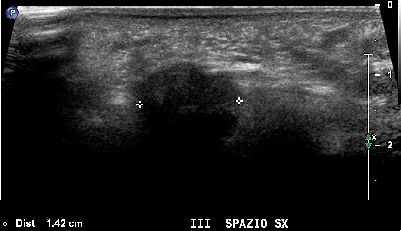

Neuroma di Morton del terzo spazio intermetatarsale (img. 02) Neuroma Morton 02